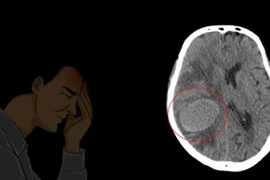

Có tiền sử khỏe mạnh và duy trì việc chơi thể thao đều đặn, bỗng nhiên thấy yếu nửa người, người đàn ông 75 tuổi (Phú Thọ) đi khám bất ngờ phát hiện mắc ung thư phổi giai đoạn cuối đã di căn não.

Di căn não là biến chứng thường gặp ở nhiều loại ung thư nhưng đặc biệt phổ biến ở bệnh nhân ung thư phổi. Trong số những bệnh nhân di căn não, xuất phát từ ung thư phổi chiếm 40-50% các trường hợp.